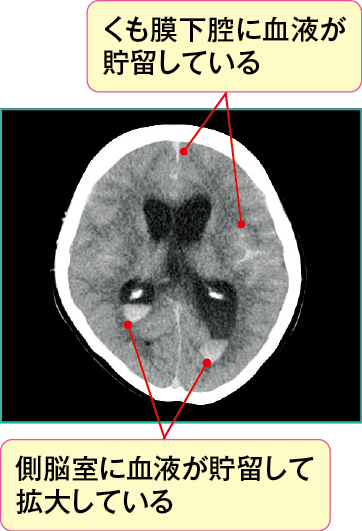

図2において、脳室は拡大し、側脳室とくも膜下腔に血液を示す高吸収域(=白い)を認めており、急性水頭症を起こしています。

本症例は椎骨動脈の解離性動脈瘤破裂によるくも膜下出血発症直後の状態です(Hunt&Hess分類のGradeⅡ、くも膜下出血の画像の見方とケアでの活用ポイント参照)。

くも膜下出血によりくも膜下腔に流出した血液は、脳溝に血液が貯留し、さらにくも膜下腔から側脳室へと血液が流れ、側脳室に血液が貯留していることがわかります。

くも膜下腔に貯留した血液が髄液を吸収する部位に付着することで生じる吸収障害を認め、急性水頭症を合併しています。

急性水頭症は、くも膜下出血のみでなく脳室内穿破を伴う脳出血でも生じる可能性があります。また、出血による水頭症は吸収障害による交通性水頭症のほかに、血液が脳室の出入口で固まることで循環障害を認め、非交通性水頭症を起こすこともあります。

関連する脳機能 くも膜下出血によりくも膜下腔や脳室内に血液が流れ込み、脳室内の内容量(髄液や血液)が急激に増え、頭蓋内圧を亢進させます。頭蓋内圧が亢進すると、意識障害や頭痛、嘔気 ・ 嘔吐といった急性頭蓋内圧亢進症状が出現します。さらに、頭蓋内圧亢進が進むと脳は頭蓋骨内で押され、脳ヘルニアを起こす可能性があります。脳ヘルニアをきたすと死に至る危険性もあります。

図2の症例では急性水頭症により頭蓋内圧が亢進し、急性頭蓋内圧亢進症状として意識障害と瞳孔不同が出現していました。